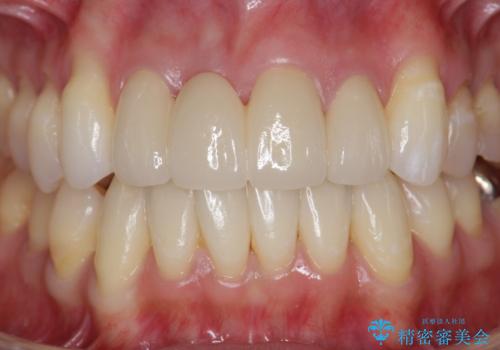

吸収し喪失した前歯、ブリッジによる審美性の回復

上顎4前歯は、根管治療の既往があり、虫歯も見られたことからブリッジによる治療で審美性の回復を行うとともに臨在歯の虫歯もセラミック治療を行っていきます。

- 44万円(仮歯・ジルコニアクラウン×4)費用は治療当時の料金となります

欠損部の歯ぐきの量が足りない場合は、移植を行い歯肉を増大させることもありますが、今回は仮歯で様子を見た結清掃性・審美性に問題が出なかったので行いませんでした。